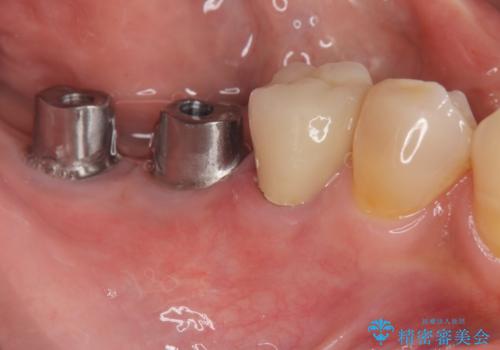

奥歯から膿のにおいがする インプラントによる機能回復

- 「奥歯で噛むと痛い、いつも膿のにおいがして不快、改善してほしい。」と治療を希望され来院されました。

精査した結果、奥歯の根は破折しており抜歯を避けられない状況でした。

咬合力が強く、その他の歯の破折も防ぐために奥歯の咬合機能をインプラントを用いて回復する治療計画を立てます。

- 99万円(インプラント×2・チタンカスタムアバットメント×2・ジルコニアクラウン×2・仮歯×2)費用は治療当時の料金となります